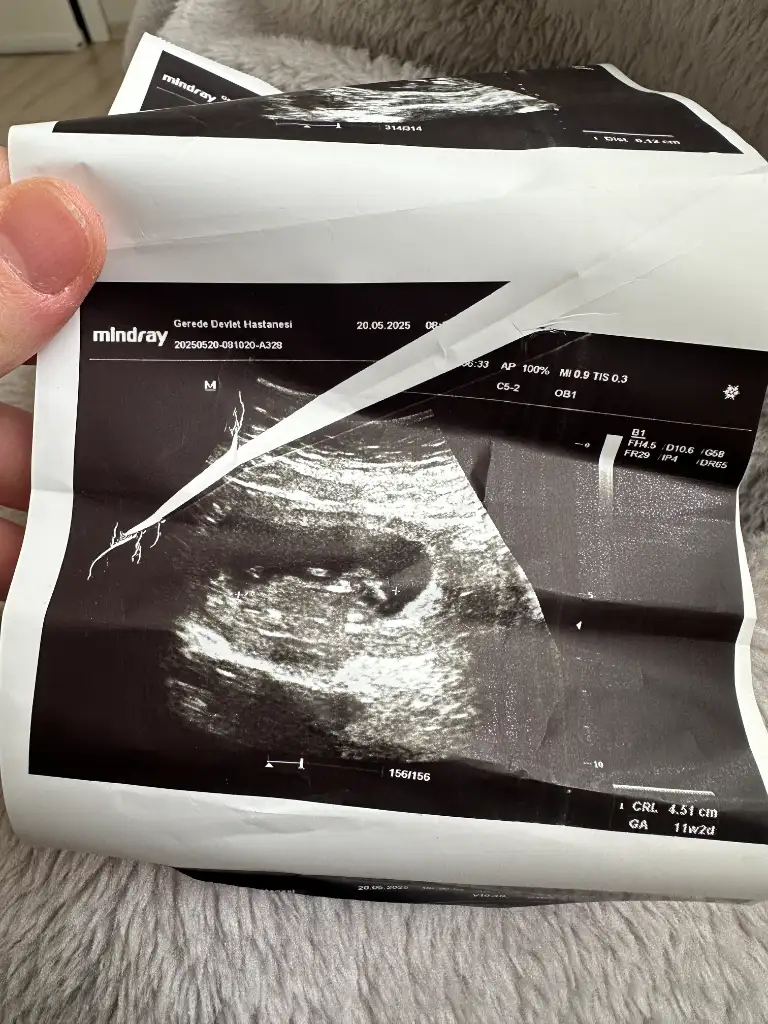

Ultrason görüntüsüne dayanarak gebeliğin yaklaşık 11. haftasında olduğunu görüyorum (aşağıda CRL ve GA bilgisi var). Bu haftalarda bebek henüz cinsiyetini ultrasonla güvenilir şekilde belli edecek kadar gelişmemiştir. Cinsiyet tahmini genellikle 13. haftadan itibaren daha net yapılabilir, ancak en doğru sonuçlar 16. haftadan sonra elde edilir.

1. hafta civarında “nub theory” (tüberkül teorisi) gibi yöntemlerle tahmin yapılmaya çalışılabilir ama bu yöntem bilimsel olarak kesin değildir ve yüksek hata payı içerir.

• Bu görüntüde cinsiyet tahmini yapmak şu an için mümkün değil.

• En doğru tahmin için birkaç hafta sonra tekrar ultrason yaptırmanız önerilir.

Evet canım tam 11 haftalık onu doğru bilmiş